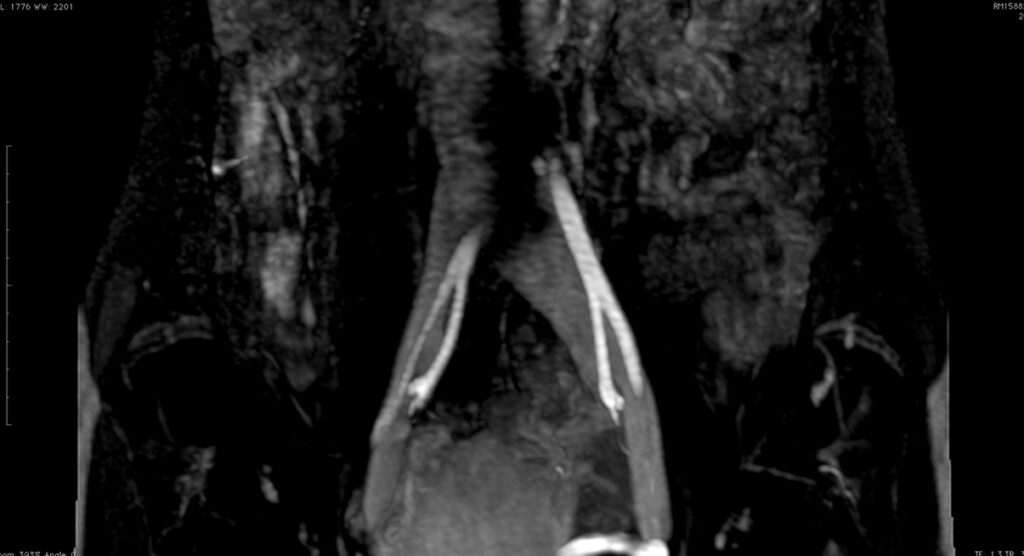

Fig. 8 y Fig. 9. AngioRM demostrando la dilatación de la VICI luego del pasaje entre AICD y la columna.

Se corrobora el diagnóstico presuntivo con flebografía y angioresonancia, observándose compresión de la VICI entre la columna y AICD y su dilatación distal (Fig. 8 y Fig. 9).